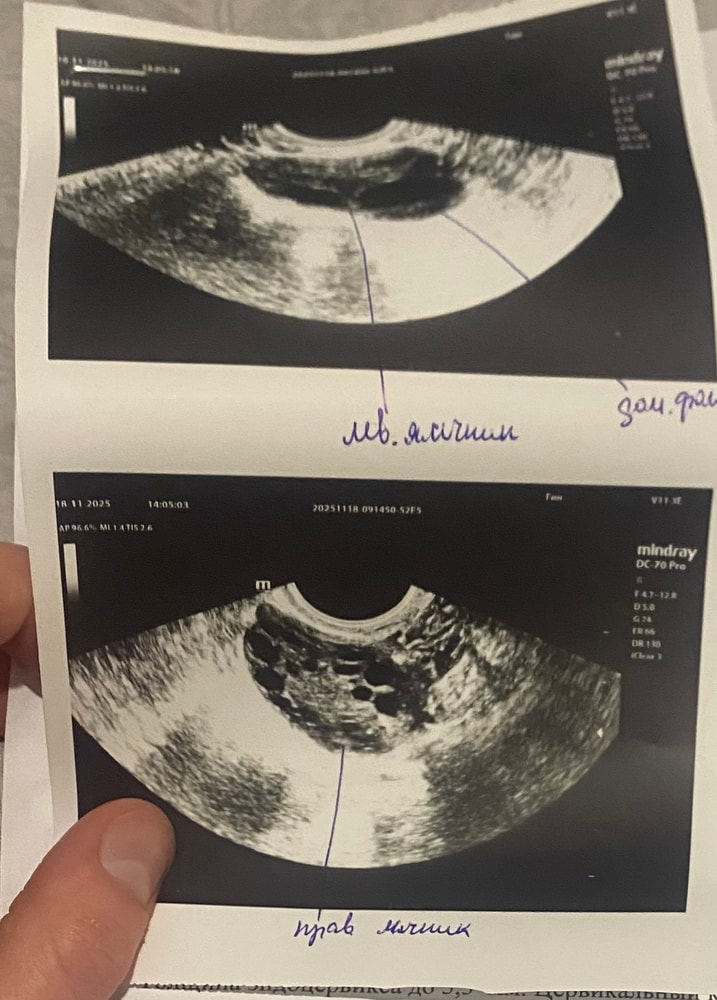

У меня один яичник мультифолликулярный. Вам бы пройти обследование на гормоны. С МФЯ сложнее забеременеть и выносить малыша (если есть проблема с гормонами) Надо дообследоваться.

18.11.2025